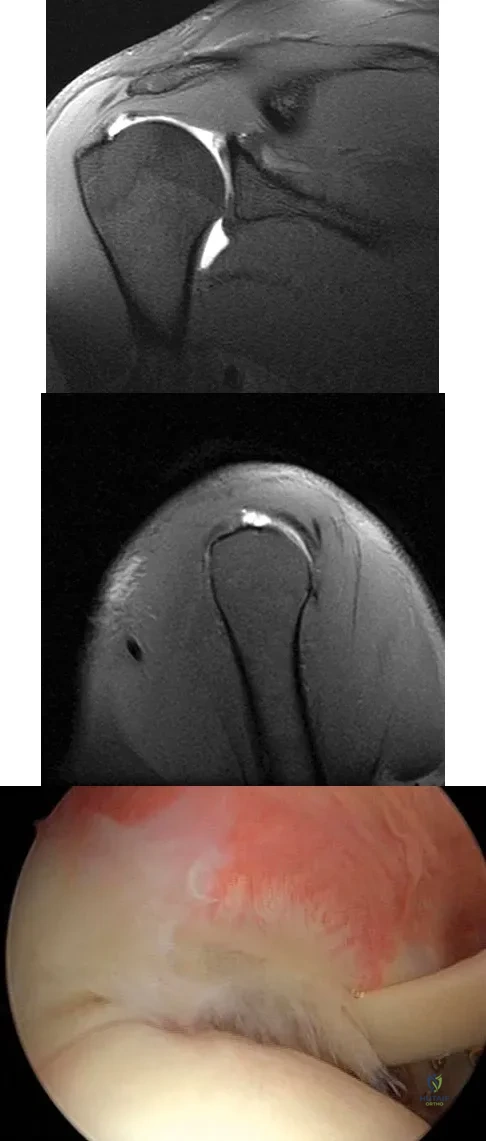

A 30-year-old man has had intermittent swelling of his right ankle for the past 6 months. He denies any history of trauma. Radiographs reveal osteolytic changes on both sides of the joint. An axial CT scan and a T2-weighted MRI scan are shown in Figures 40a and 40b. He undergoes surgical excision. An intraoperative photograph and a biopsy specimen are shown in Figures 40c and 40d. What is the most likely diagnosis?

Pigmented villonodular synovitis often presents with intermittent swelling and minimal pain. It often occurs around joints but may be found around tendon sheaths and bursal linings. Periarticular erosions involving both sides of joints are typical, and multiple joint involvement has been described. Portions of low-signal intensity on T1- and T2-weighted images are characteristic of hemosiderin-laden processes. High-signal content is suggestive of high water content. The combination of low-signal intensity areas in intra-articular lesions with or without osseous destruction is diagnostic of pigmented villonodular synovitis. Aspiration reveals bloody or brownish fluid. The treatment of choice is synovectomy performed arthroscopically or open. Recurrence is common. Walling AK: Soft tissue and bone tumors, in Coughlin MJ, Mann RA (eds): Surgery of the Foot and Ankle, ed 7. St Louis, MO, Mosby, 1999, pp 1007-1032.